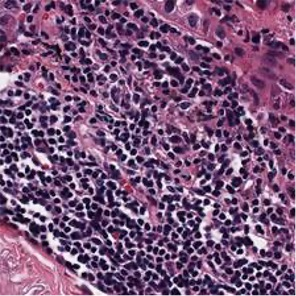

Multiple instance learning (MIL) is a powerful approach to classify whole slide images (WSIs) for diagnostic pathology. A fundamental challenge of MIL on WSI classification is to discover the \textit{critical instances} that trigger the bag label. However, previous methods are primarily designed under the independent and identical distribution hypothesis (\textit{i.i.d}), ignoring either the correlations between instances or heterogeneity of tumours. In this paper, we propose a novel multiplex-detection-based multiple instance learning (MDMIL) to tackle the issues above. Specifically, MDMIL is constructed by the internal query generation module (IQGM) and the multiplex detection module (MDM) and assisted by the memory-based contrastive loss during training. Firstly, IQGM gives the probability of instances and generates the internal query (IQ) for the subsequent MDM by aggregating highly reliable features after the distribution analysis. Secondly, the multiplex-detection cross-attention (MDCA) and multi-head self-attention (MHSA) in MDM cooperate to generate the final representations for the WSI. In this process, the IQ and trainable variational query (VQ) successfully build up the connections between instances and significantly improve the model's robustness toward heterogeneous tumours. At last, to further enforce constraints in the feature space and stabilize the training process, we adopt a memory-based contrastive loss, which is practicable for WSI classification even with a single sample as input in each iteration. We conduct experiments on three computational pathology datasets, e.g., CAMELYON16, TCGA-NSCLC, and TCGA-RCC datasets. The superior accuracy and AUC demonstrate the superiority of our proposed MDMIL over other state-of-the-art methods.